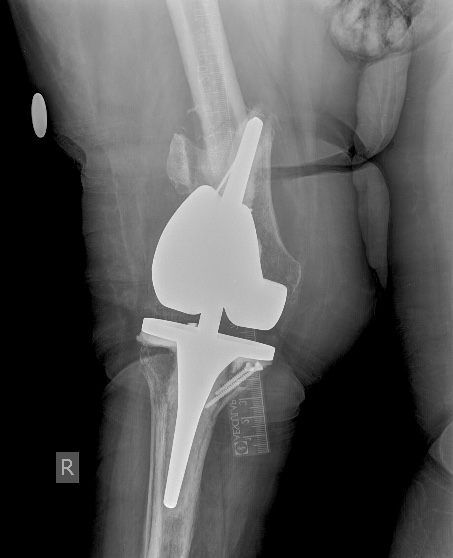

[Ortho] Перипротезный перелом бедра у ребёнка

Оптимальное решение - закрытый остеосинтез интерамедуллярным стержнем с

удлинением ножки эндопротеза. Пример в приложении. Делает такие стержни

предприятие ЦИТО.

Имя     : Бедро AP.0003.jpg